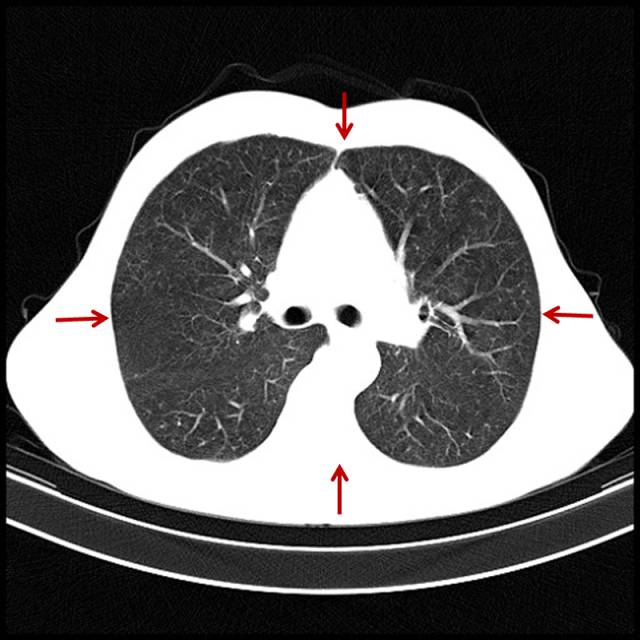

吸烟导致的中重度肺气肿

男,65岁,咳嗽、气短、吸烟几十年。

图片

图7

双肺多个小无肺纹区。有自觉症状,患者基本会意识到气短与吸烟有关。此类患者戒烟不戒烟,完全取决于自己的毅力。相当一部分患者已经成瘾,或者说成习惯了,会说慢慢戒、减量。我见过一天最多能吸5盒烟的。